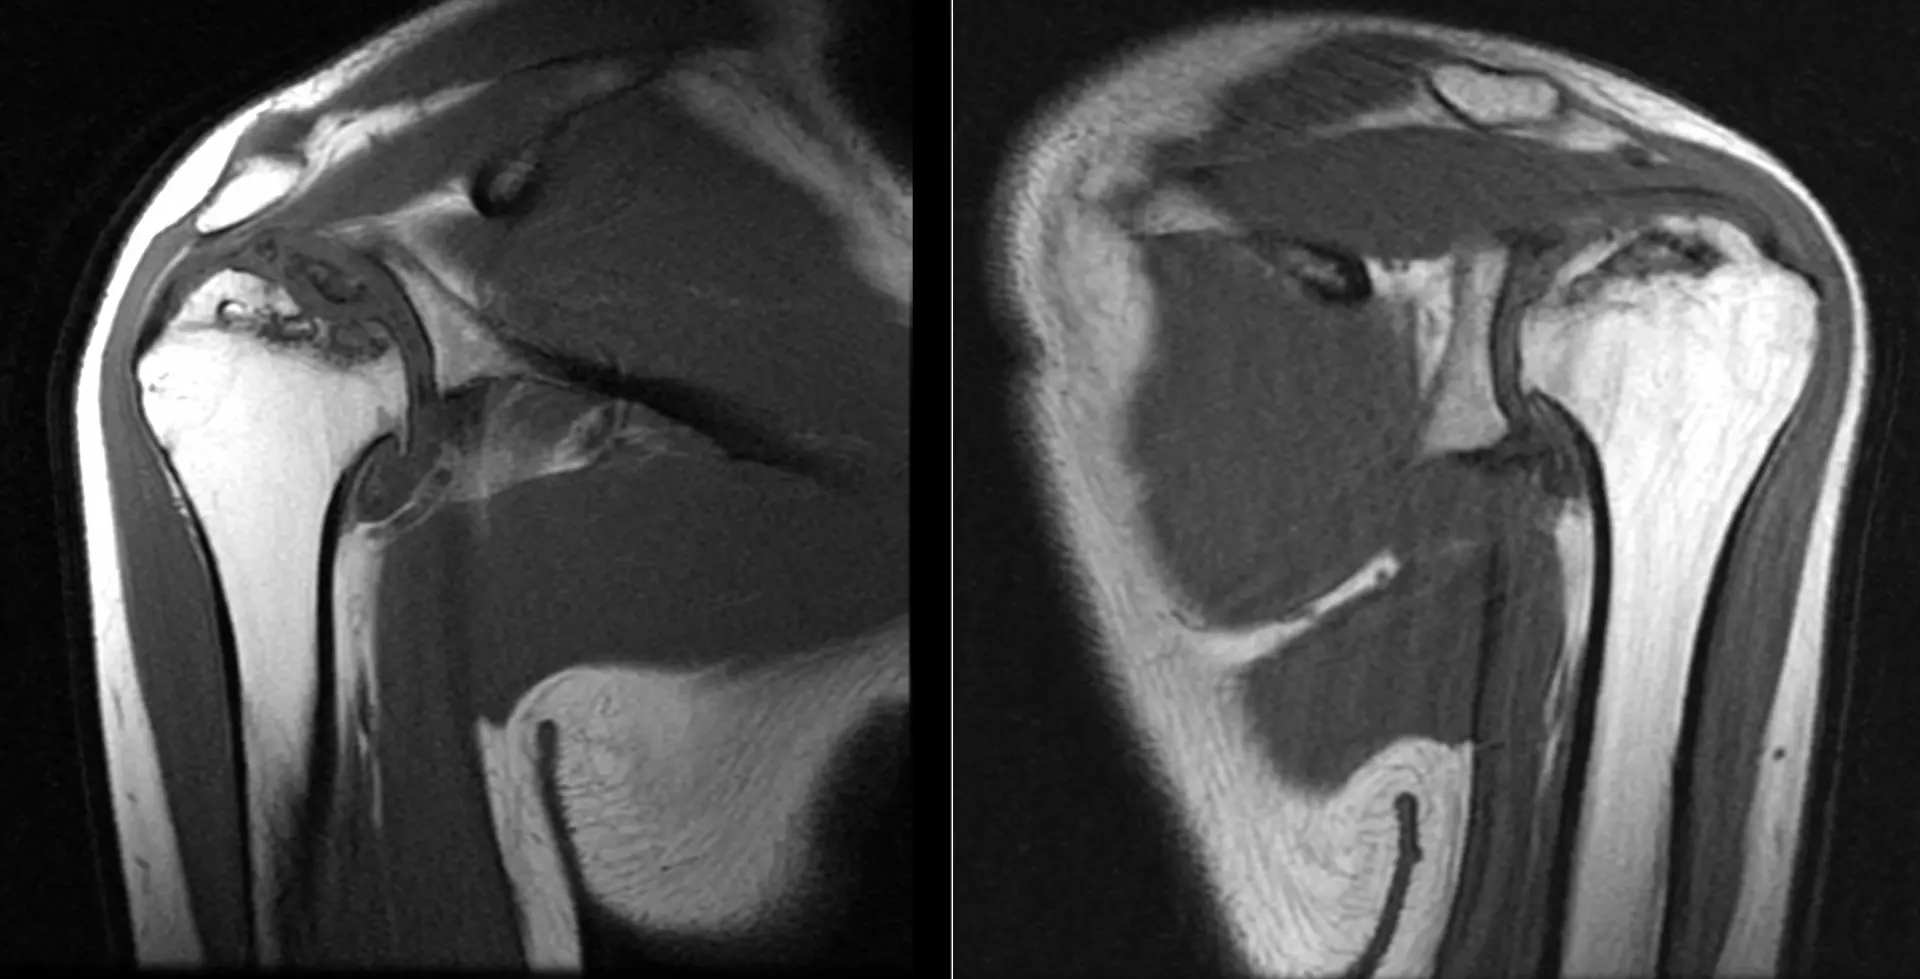

Вот такие плечики у пациента 29 лет! Во время эпидемии COVIDa-19 перенёс тяжёлую форму, лечили, в том числе, высокими дозами кортикостероидов, так что остеонекроз, который мы имеем возможность видеть в головках плечевых костей, по всей видимости, развился, как осложнение этого вида терапии. Хотя, при этой инфекции возникает ещё и гиперкоагуляция, которая и сама по себе является фактором риска развития некроза костей. В литературе такие случаи описаны и известны, есть описания развития остеонекроза даже четырёх костей одновременно (головок бедренных и плечевых костей), причём, развился он аж через полгода после окончания терапии. В нашем случае справа некроз привед к фрагментации головки плеча. Понятное дело, что функции плечевых суставов нарушены, в том числе, за счёт развития грубого вторичного артроза. Видимо, тотальная артропластика потребуется...